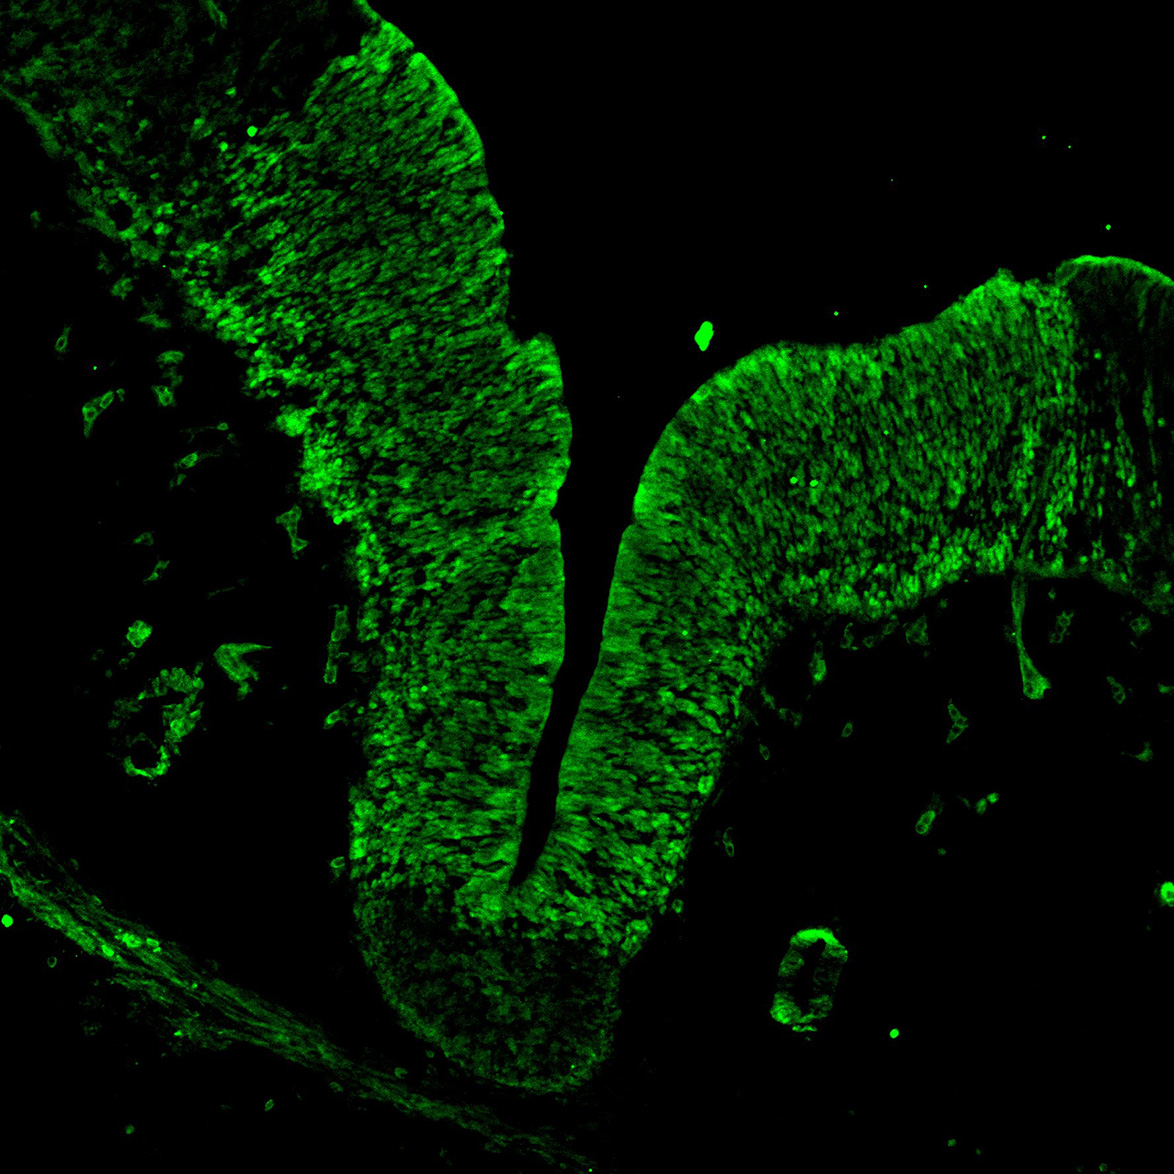

An anatomical analysis of the developing human midbrain from 6 post-conceptional weeks (PCW) to 22 PCW reveals increased tissue complexity, characterized by the emergence of dopaminergic nuclei, as highlighted by immunofluorescence analysis for tyrosine hydroxylase (TH).

MAP2

11PCW human midbrain